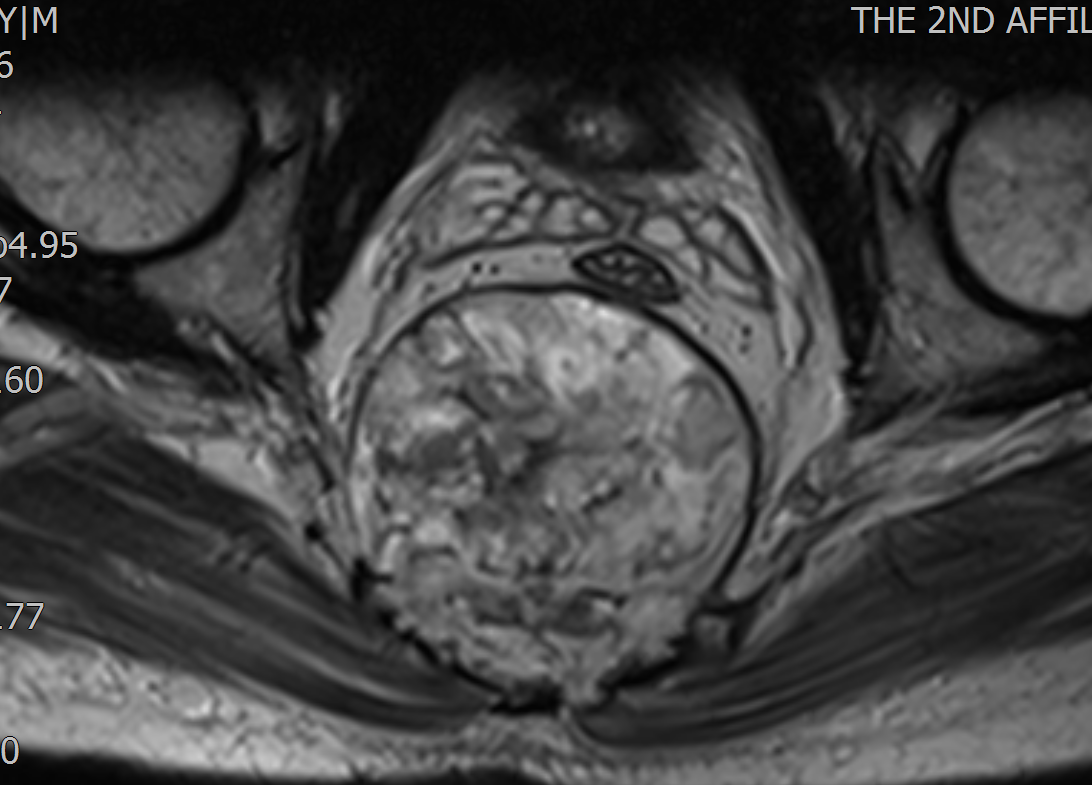

患者李某,腰臀部疼痛半年,加重伴排便障碍1月来我院就诊。赵波副主任医师接诊病人后,凭借丰富的经验察觉患者有盆腔肿瘤可能,给患者安排盆腔CT、MRI等检查后发现骶骨下方有一个直径约10cm的巨大肿块,前方压迫直肠,上下方挤压髂内大血管和坐骨神经,肿瘤侵犯S3-5椎体及神经根并向周围生长,肿瘤继续发展将进一步压迫直肠及腹腔脏器组织,已严重影响患者的日常生活。,科内大讨论和全院肿瘤MDT讨论认为患者骶骨原发性脊索瘤可能性大,脊索瘤放化疗效果不佳,手术完整切除为治疗的首选方法。与患者及家属充分沟通后,决定为患者行肿瘤切除手术。

为预防术中意外情况,保证患者手术安全,赵波副教授、欧阳鹏荣主治医师在术前为患者进行骶尾骨及肿瘤的计算机三维重建、计算机模拟手术、3D模型打印,为患者制定了精密的手术方案。最终,由王栋教授主刀,在赵波副教授、欧阳鹏荣主治医师、李宇欢住院总医师配合下,在麻醉科李伟副主任、严百惠副教授、李亚护士的保驾护航下为患者成功进行了骶骨肿瘤切除术。在保留双侧骶2神经根的前提下,成功切除骶3及以下骶尾骨,并瘤外完整切除肿瘤,术中出血仅600ml,手术圆满完成,术后患者双下肢感觉运动良好。在脊柱与骨肿瘤病区赵辰护士的精心护理下,患者逐渐从手术创伤中恢复,腰臀部疼痛消失,大便恢复正常。最终病理检查诊断为脊索瘤,安排好后续治疗后,患者顺利步行出院。